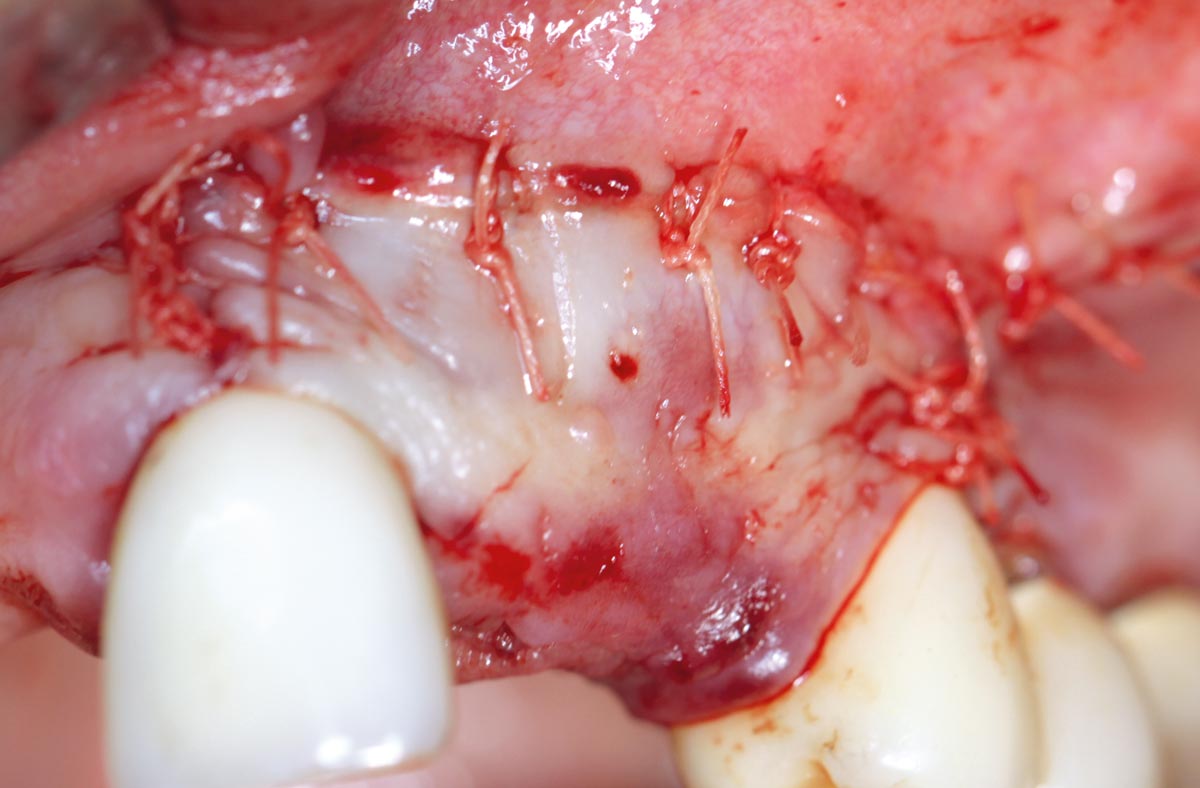

Restoration of all four incisors with two maxgraft® bonering - Dr. B Giesenhagen

Initial situation pre-op: Central incisors with mobility 3